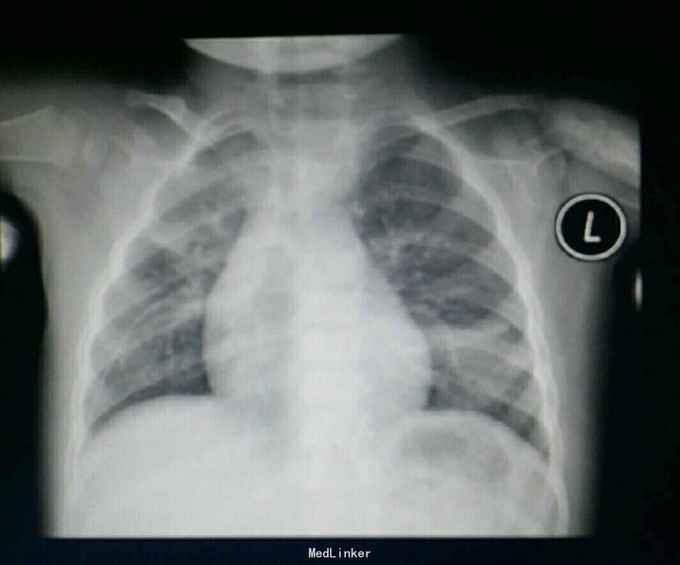

胸片,CT.如图,最后一图为一周后复查胸片。

注意随诊,及时复查。